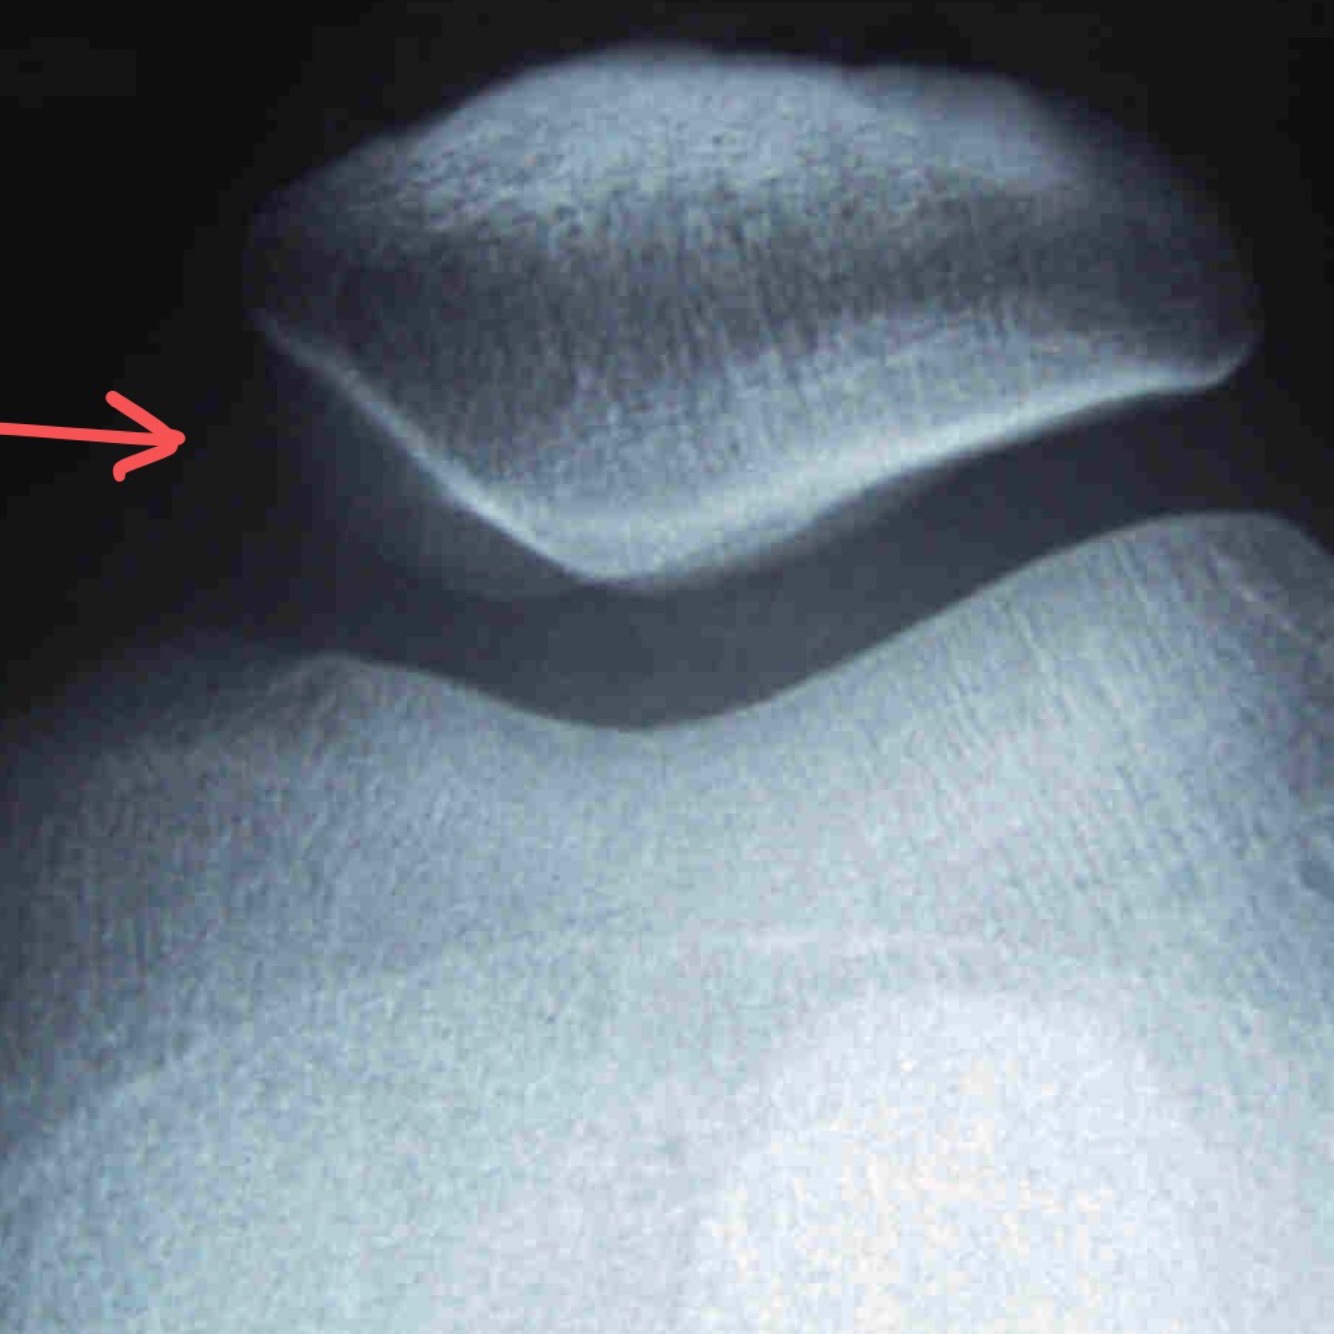

Q

Qui suis-je?

• Flexion du genou à 45 ̊ la plus fréquente (60-90 degrés peuvent être faits)

• Évaluation des surfaces des condyles fémoraux et de la patella

• Évaluation si presence de subluxation patellaire (alignement)

A

Projection axiale de la patella